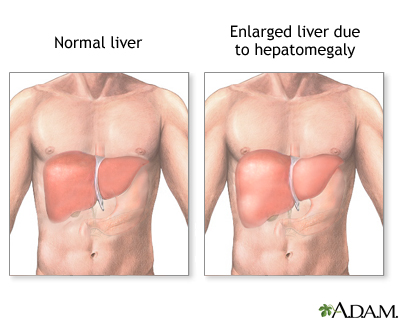

Enlarged liver refers to swelling of the liver beyond its normal size. Hepatomegaly is another word to describe this problem.

If both the liver and spleen are enlarged, it is called hepatosplenomegaly.

The lower edge of the liver normally comes just to the lower edge of the ribs on the right side. The edge of the liver is normally thin and firm. It cannot be felt with the fingertips below the edge of the ribs, except when you take a deep breath. It may be enlarged if a health care provider can feel it in this area.